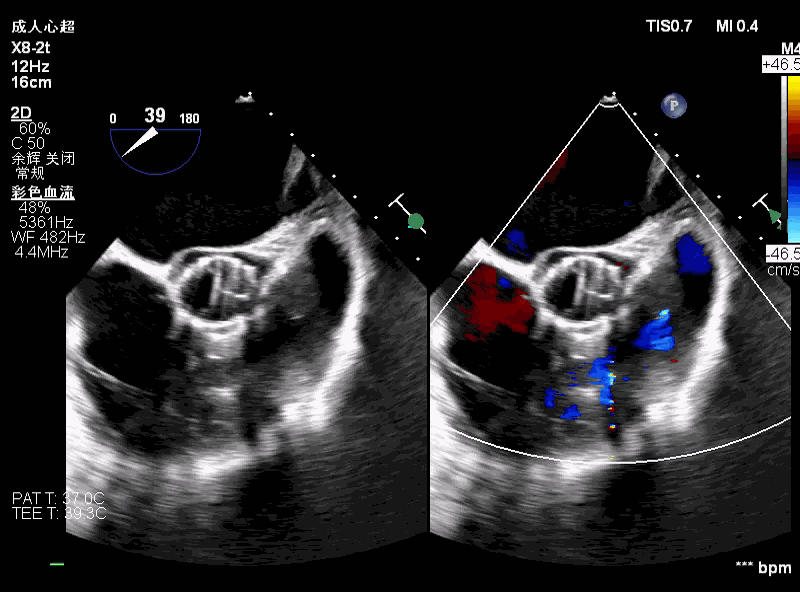

降低原因 — 二尖瓣?

● 考虑超硬导丝缠绕腱索导致二尖瓣关闭受限,予以超声检查。

术前评估主动脉瓣可见中大量反流,二尖瓣轻微反流。

术中超声可见超硬导丝缠绕,二尖瓣大量反流,引起血压无法回升。

撤出输送器,重新调整超硬导丝大小及位置,血压回升,患者情况稳定。